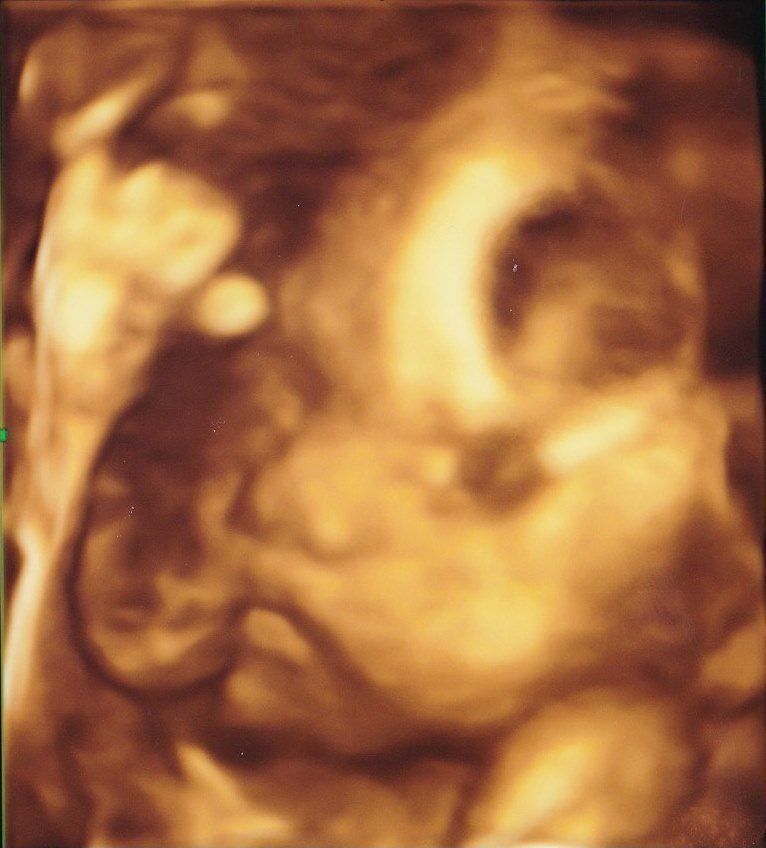

妊娠24週目の4Dエコー写真 顔の表情がわかり、少しだけ親近感が湧く

推定体重=854g

お顔のアップの4D画像です。手を顔の前においてこちらを見ていて、少し心配そうなお顔に見えました。おなかの中でぽこぽこしたり、ぐるぐるしたりする感覚がありましたが、いまいち胎動なのかはわからず、「あ、動いた」と感じるような胎動に感動することがないまま日々が過ぎました。アイスクリームとチョコレートが大好きになり、我慢するのがつらかったです。